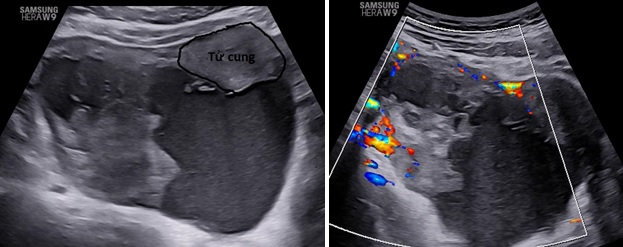

– Siêu âm: Tử cung và buồng trứng (T) bình thường, buồng trứng (P) không quan sát thấy. Từ cùng đồ sau lan qua hố chậu (P) có 1 khối echo hỗn hợp không đồng nhất, kích thước# 105x 98x 59 mm, bên trong có nhiều mảng echo dày bờ không đều, di động khi di chuyển đầu dò, có tăng sinh mạch máu mức độ 3 Ở ngoại vi khối này có hình ảnh mô buồng trứng bình thường. Dịch cùng đồ# 8 mm.

– Chẩn đoán siêu âm: Theo dõi khối huyết tụ thành nang (HTTN) chưa loại trừ khả năng: u đơn thùy buồng trứng (P) có mảng xuất huyết bên trong.

Hình 1: Mặt cắt ngang qua bụng trên thang xám và Doppler, khối u nằm sau tử cung lệch qua hố chậu phải có khối phản âm hỗn hợp không đồng nhất, có tăng sinh mạch máu ngoại vi

Hình 3: Siêu âm ngã bụng thang xám cắt dọc và ngang cho thấy khối u nằm mặt sau tử cung lan qua hai bên hố chậu.